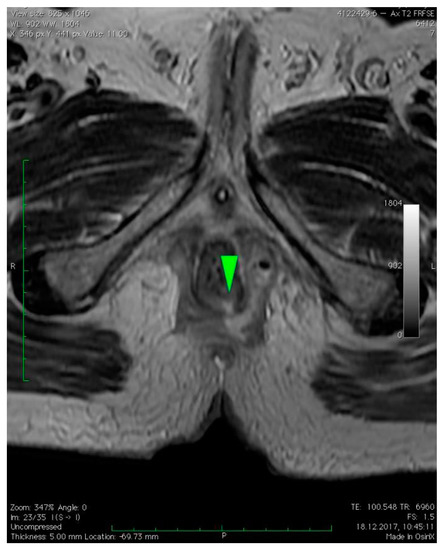

2.2. Radiologic Imaging

3. Case Presentation